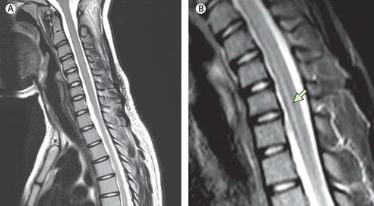

根据医生的指导,护士们立即给小张进行了气管插管,以确保他的呼吸通畅。接着,医生对小张进行了严格的神经学检查、脑脊液检查以及磁共振成像等检查,并最终确诊为急性脊髓炎。

于勤.急性脊髓炎的MRI诊断和鉴别诊断研究[J].中国农村卫生, 2017(02):42+32.